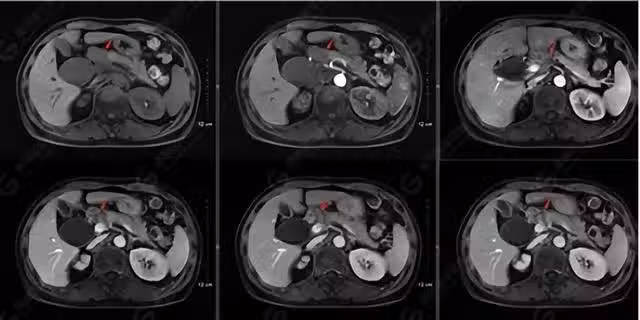

55歲男子頻繁腹瀉半年,反覆檢查腸鏡正常,最終確診胰腺癌晚期

黃先生面對這個結果感到很驚訝,自己為什麼一點感覺都沒有,突然就得胰腺癌了呢?醫生告訴他,這種病的致病元兇很可能和自己平時的暴飲暴食、過度飲酒吃肉和日常作息有很大關係。

腹瀉並不只是胃腸病,尤其是在排除飲食因素之後,還出現的長期腹瀉更不應該簡單認為是胃腸道異常所致,一些肝病、胰腺病、甲狀腺疾病也會引起反覆腹脹腹痛腹瀉的症狀,同時還會伴有相應臟器功能異常的表現。